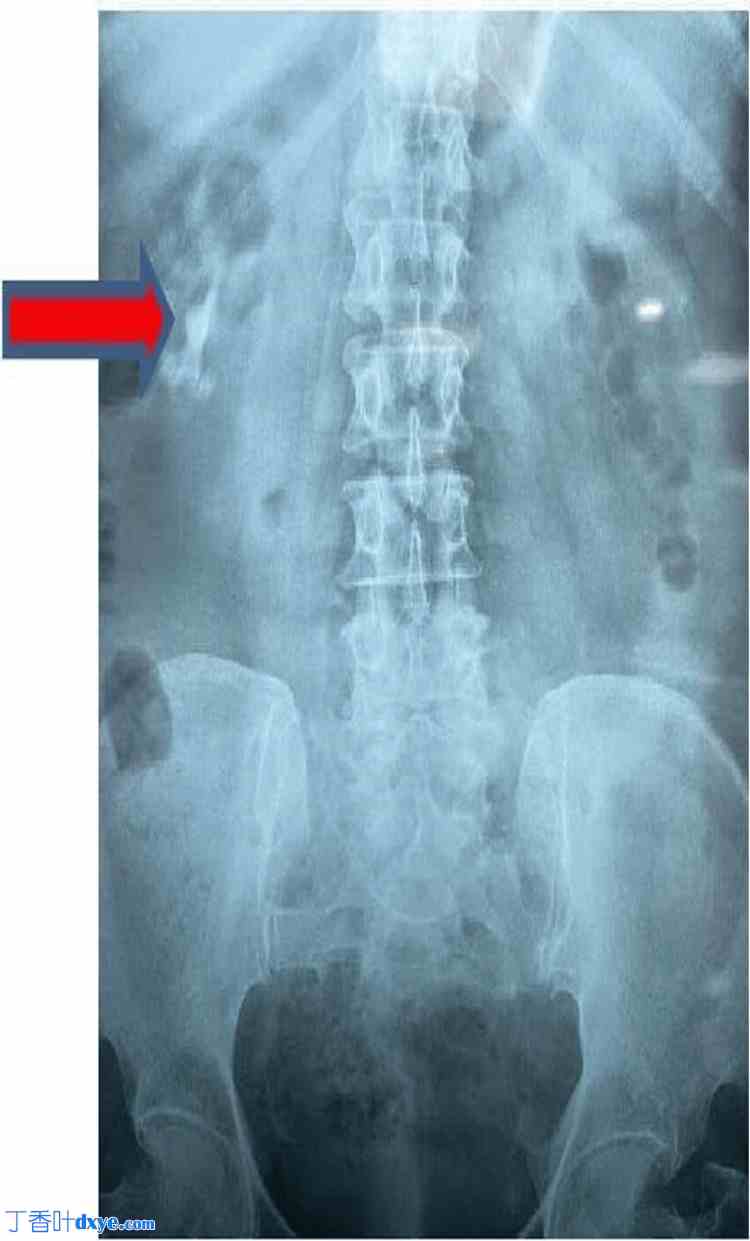

C臂X光片显示结石完全清除。术中放置双J管。术后肾脏、输尿管和膀胱平片(KUB)显示无残余结石(图5)。

图5. 术后肾脏、输尿管和膀胱平片提示无残余结石。